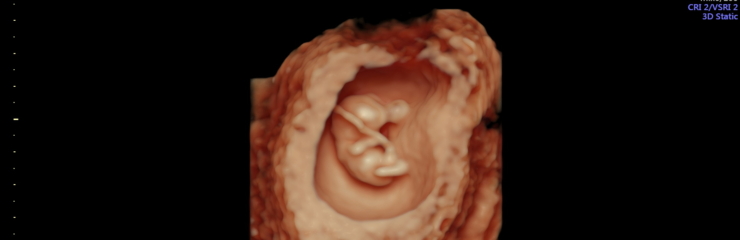

Umbes millimeetrisuurune munarakk on kinnitunud emaka limaskesta külge.

Hakkab moodustuma platsenta.

Hakkavad arenema soolestiku, kopsude ja närvisüsteemi alged. Osa rakke hakkavad moodustama nahka, lihaseid ja veresooni.

Loode:

Ultraheliuuringul on loode nähtav. Hakkab moodustuma loote selgroog ning ajul on moodustunud kaks sagarat. Lootel hakkavad arenema käed, jalad ja nägu. 8. nädalal on lootel moodustunud kõik peamised siseorganid. Süda lööb korrapäraselt. Loode on umbes 4 sentimeetrit pikk. Kuni 14.

nädalani mõõdetakse lapse pikkust peast seljani (CLR).